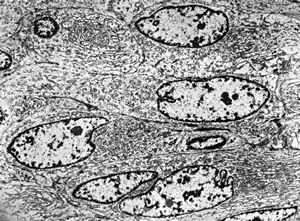

F,25y. | myopathy - atrophic and regenerating muscle cells

M,2y. | myopathy - regenerating muscle cell